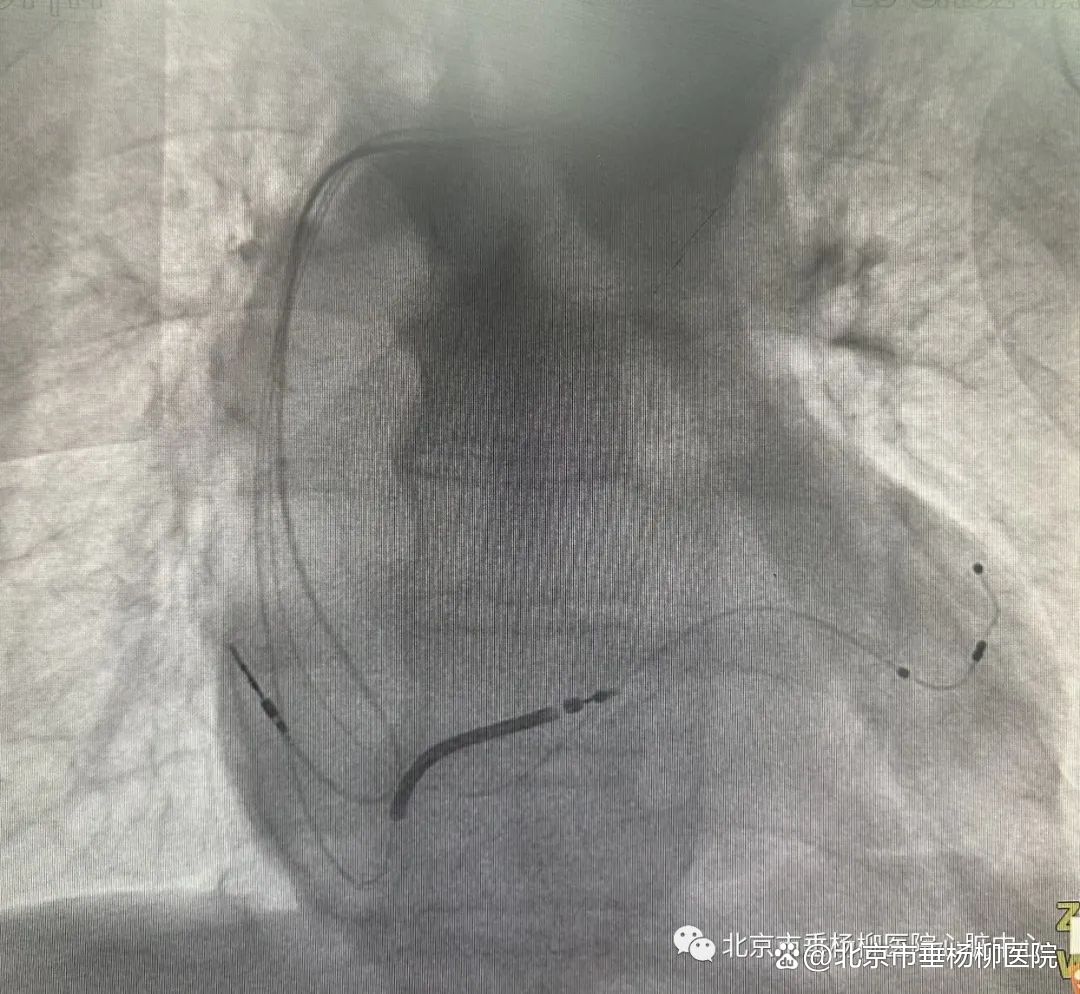

▲巨大的心脏中植入的三强起搏除颤电极果然,术后患者的腹透效果不佳,自行腹透只有100毫升的超滤量,完全无法平衡每日的必须入量。肾内科主任余永武高度重视这个病例,在周末仍安排了专业的医生和透析护理团队到病房现场指导上机腹透,并为这例患者专门临采了高浓度的腹透液进行透析。经过肾内科专业的床旁腹透治疗,患者的出入量终于可以达到心衰治疗需要的平衡量。然而,术后第三日,心脏重症病房需要接收心内科病房转入的需要呼吸支持和床旁血滤的新冠阳性患者,CCU病房患者面临着高度的新冠感染风险,为了避免新冠感染给器械植入后的患者带来的双重感染风险,皮林会同CCU护士长肖光青和7D病区护士长梁志青,周日从家中赶到医院开会讨论后决定在CCU之外,在7D抢救间紧急开辟转化新冠阳性CCU,将病房的三例新冠阳性患者集中收治在7D病区抢救间进行救治。CCU和心内的医疗护理紧急抽调协调人力,当日傍晚就完成了重症病房的转化,新冠阳性的患者顺利进行了呼吸支持和床旁血滤治疗,而CCU内的重症患者也避免了感染的风险。患者术后没有感染,切口愈合良好,术后7日拆线顺利出院。心力衰竭是众多心血管疾病发展的终末阶段,患者反复住院、预后差、发生室速室颤引起猝死风险高,其5年死亡率高达50%。三腔起搏除颤器是在心脏再同步化的基础上加入了除颤的功能,通过使左右心室收缩同步改善心功能,还能在患者发生室速或室颤时通过电复律治疗恶性室性心律失常、避免猝死。对于猝死高风险的心力衰竭患者,可以通过三腔起搏除颤器可以植入改善心功能、减少猝死风险。医院心内科对心力衰竭的治疗,从优化的药物治疗到器械植入,医疗技术水平不断提升,为患者提供全方位的治疗,努力成为心力衰竭患者的守护神。